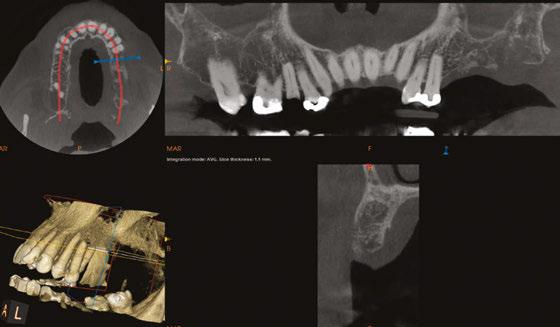

The protocol for immediate loading of fullarch implants includes the extraction of all non-salvageable teeth, implant placements, abutment placements, intraoral scans (Itero®) with scan bodies placed on the abutments, and in-house milling (Zirconzahn®) on the day of the surgery. The information referred to the esthetics, and vertical dimension is gathered with the extraoral 3D facial scans with Face Hunter software (Zirconzahn), 2D photographs, and intraoral scans prior to surgery. The day of extractions and implant surgery, abutments are placed and scanned, and initial designs are merged with anatomical landmarks. The polymethyl methacrylate (PMMA) prosthesis is milled in-house following the merging of the initial and post-implant placement digital scans and the design of the new teeth the day of the surgery.

Clinical step-by-step demonstration of the complete digital flow

Dr. Siranli starts by analyzing the patient’s facial esthetics to design a personalized smile and then combine 3D facial and dental scans (Figure 1).

Patient’s resting and smiling incisal display, vertical dimension of occlusion, and intraoral maximum intercuspation are evaluated clinically and through Face Hunter software (Zirconzahn®) prior to the surgery (Figures 2-4). A detailed smile design prescription gets created after this point. In this particular case presentation, the smile design prescription was:

• Bring the maxillary incisal edge down 8 mm.

• Bring the mandibular incisal edge down 4 mm.

• Bring the mandibular bone level down 5 mm.

• Labiolingually, use mandibular anterior as a guidance.

• Open the vertical dimension of occlusion 6 mm.

The day of the surgery, intraoral markers are placed, and intraoral scans are captured prior to surgery. The remaining teeth are extracted, implants and muti-unit abutments (Neodent®, Straumann) are placed (Figure 5), and abutment scan bodies

Figure 1: Face Hunter 3D facial scans merged with intraoral scans. Green color represents the new digital design of the smile design Figures 2-4: 2. Resting incisal display. 3. Smiling incisal display. 4. Maximum intercuspation Figure 5: Implants, multi-unit abutments, and scan bodies placed Figure 6: Post-surgery intraoral scans

get connected. Intraoral scans are done again after the surgery (Figure 6), and pre- and post-surgery scans are overlapped to mill the PMMA teeth the day of the surgery. While I do own a 3D printer, I like milled PMMAs more since that provides more shade options with the lighter colors. I also find milled PMMAs are stronger than the printed PMMAs.

PMMA gets milled (Figure 7) and delivered the day of the surgery with a very passive fit (Figures 8 and 9).